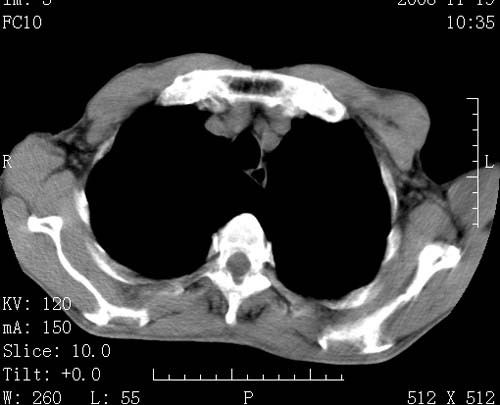

标题: CT16691:m 67 胃镜确诊食管下段及贲门癌 [打印本页]

标题: CT16691:m 67 胃镜确诊食管下段及贲门癌

术前查体,双肺部结节是转移?结核?请点评

转移 隆突下淋巴结亦肿大

首先考虑转移,纵隔内淋巴结亦肿大;

1)符合食管癌表现。2)两肺及纵隔淋巴结多发性转移瘤。3)左肺上叶舌段及两肺下叶炎症感染。

食管癌伴双肺转移,评述:肺部毛细血管网丰富,全身血液均快速流经肺部,癌细胞容易过滤定植,形成转移瘤,影象特点为以毛细血管末梢为中心的结节灶,边缘光滑锐利,少见有中心空洞着,不同来源的转移瘤可有各自特点,如甲状腺癌为双肺弥漫性微结节,本例有原发灶,双肺影象灶典型,左肺舌段条带状网格样伴胸膜天幕征,可视为癌性淋巴管炎。